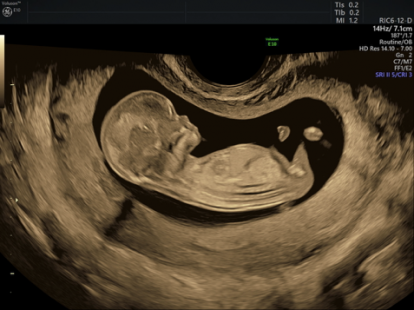

L’échographie permet d’obtenir des images grâce à des ultrasons émis par une sonde et renvoyés par le fœtus. Ces signaux sont transformés par la machine en images visualisées pendant l’examen sur un écran.

Des photos peuvent être prises au cours de l’examen mais la meilleure analyse des images se fait “en temps réel” au cours même de l’échographie et non après.

L’échographie 3D n’est pas une nécessité pour le diagnostic des anomalies.